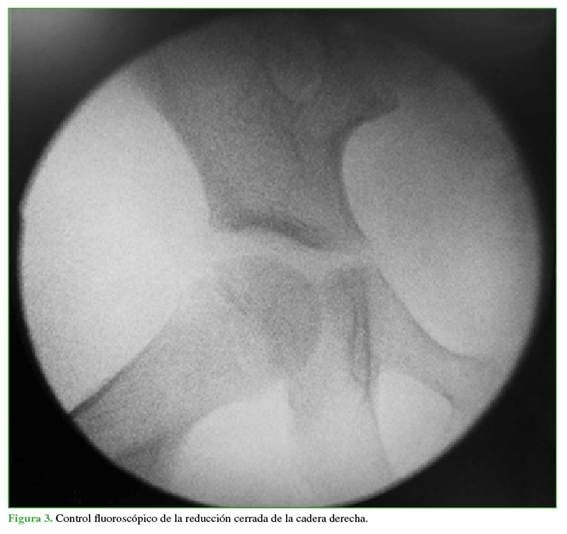

Después de estabilizar al paciente, se efectuó una reducción cerrada bajo sedación, a las 8 h del accidente. Con el niño en decúbito supino y la rodilla en flexión a 90°, se aplicó tracción longitudinal; en forma simultánea, se desplazó lateralmente el fémur proximal utilizando una banda y rotación externa, y así se consiguió una reducción clínica exitosa. Las maniobras de estabilidad fueron positivas y se comprobó la reducción mediante fluoroscopia (Figura 3).